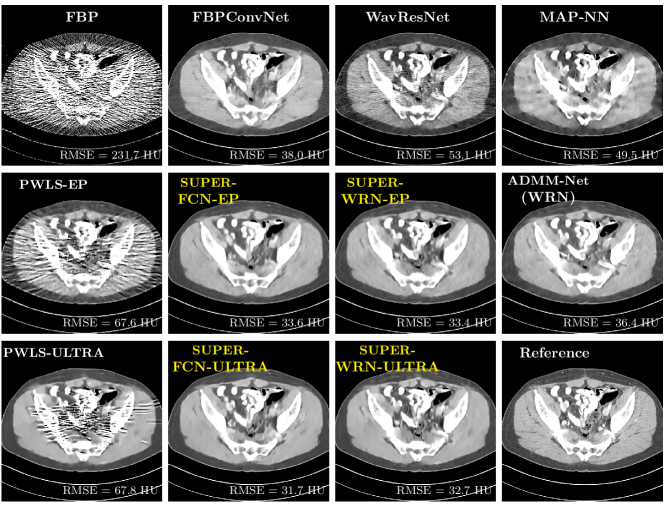

Fig. 2 shows a test example reconstructed using various methods.

Refer to caption

Figure 2: Reconstructions of slice 100 from patient L192 using various methods. The display window is [800 1200] HU.

We observe that PWLS-EP reduces the severe noise and streak artifacts observed in the low-dose FBP images, and the transform learning-based method PWLS-ULTRA further suppresses noise and reconstructs more details of the image such as the zoom-in areas. However, both methods have some blurry artifacts. The standalone FBPConvNet method heavily removes noise and streak artifacts, while introducing several artificial features (e.g., feature indicated by the arrow in the top-right box in Fig. 2). WavResNet denoises the image without introducing artifical features, but still retains some streaks around image boundaries and blurs some details (e.g., feature indicated by the arrow in the bottom-left box in Fig. 2). The state-of-the-art MAP-NN method performs slightly better than WavResNet in terms of suppressing streak artifacts, while it still loses some details as indicated in the zoomed regions. The competing plug-and-play unrolled method—ADMM-Net with WavResNet denoiser—outperforms the standalone WavResNet method, but still has some streak artifacts and blurred details. Compared to these methods, the proposed SUPER methods (SUPER-WRN-EP, SUPER-WRN-ULTRA, SUPER-FCN-EP, and SUPER-FCN-ULTRA) improve the reconstruction quality in terms of removing noise and artifacts, and recovering details more precisely. Two other example comparisons are included in the supplement (Fig. 10 and Fig. 11).